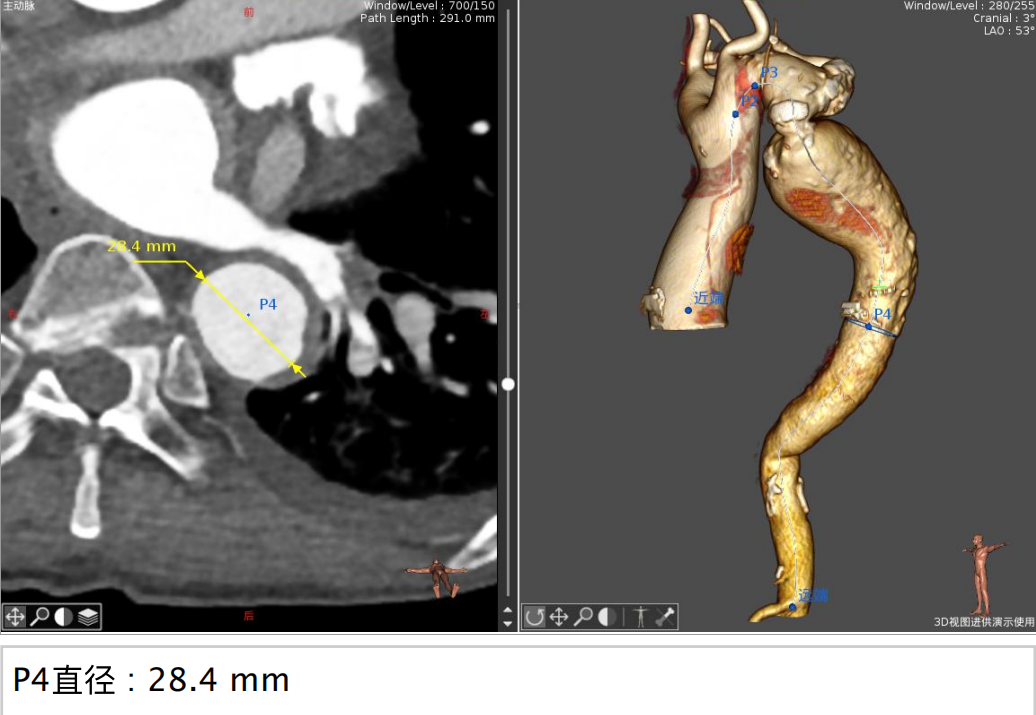

患者CT结果显示:主动脉瓣属于Type0型二叶瓣,重度狭窄并钙化,整个主动脉段非常扭曲,且在胸主动脉段有严重缩窄合并巨大主动脉瘤,双侧下肢动脉入路狭窄。同时,患者术前心脏超声提示心功能值(EF)仅17%,手术风险极高,国内外并无可供参考的手术方案和经验分享。

CT分析结果:

图示:瓣环、左室流出道、主动脉窦、升主动脉、窦管结合及瓣上结构部大小。